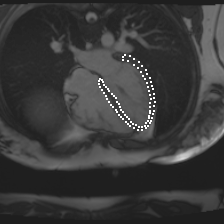

Accurate segmentation and motion estimation of myocardium have always been important in clinic field, which essentially contribute to the downstream diagnosis. However, existing methods cannot always guarantee the shape integrity for myocardium segmentation. In addition, motion estimation requires point correspondence on the myocardium region across different frames. In this paper, we propose a novel end-to-end deep statistic shape model to focus on myocardium segmentation with both shape integrity and boundary correspondence preserving. Specifically, myocardium shapes are represented by a fixed number of points, whose variations are extracted by Principal Component Analysis (PCA). Deep neural network is used to predict the transformation parameters (both affine and deformation), which are then used to warp the mean point cloud to the image domain. Furthermore, a differentiable rendering layer is introduced to incorporate mask supervision into the framework to learn more accurate point clouds. In this way, the proposed method is able to consistently produce anatomically reasonable segmentation mask without post processing. Additionally, the predicted point cloud guarantees boundary correspondence for sequential images, which contributes to the downstream tasks, such as the motion estimation of myocardium. We conduct several experiments to demonstrate the effectiveness of the proposed method on several benchmark datasets.